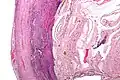

Even for clinically certain appendicitis, routine histopathology examination of appendectomy specimens is of value for identifying unsuspected pathologies requiring further postoperative management.[75] No sign of appendicitis in specimens, negative appendectomy, varies but has been estimated to occur in 13% of specimens.[76] Notably, appendix cancer is found incidentally in about 1% of appendectomy specimens.[77][78]

Pathology diagnosis of appendicitis can be made by detecting a neutrophilic infiltrate of the muscularis propria.

Periappendicitis (inflammation of tissues around the appendix) is often found in conjunction with other abdominal pathology.[79]

Classification of acute appendicitis based on gross pathology and light microscopy characteristics[80]